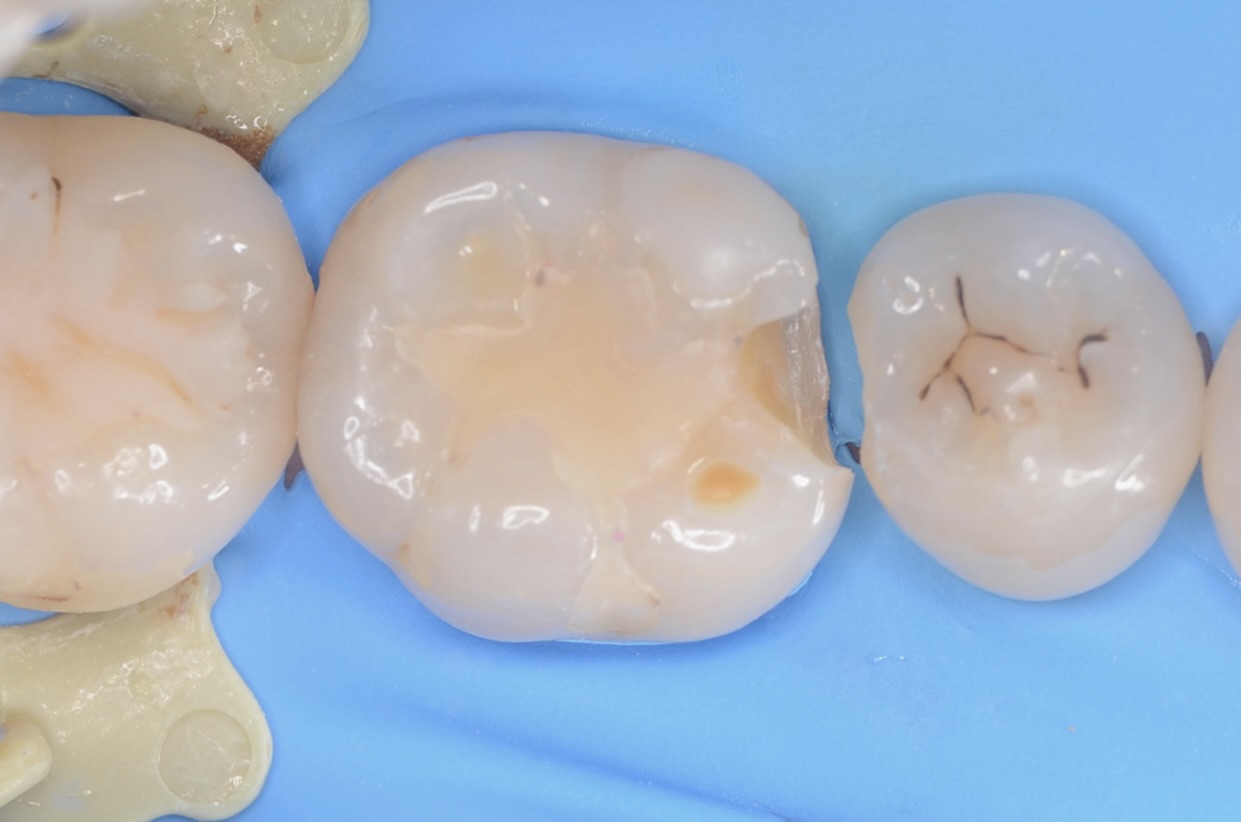

少し歯を削ったところ

齲蝕検知液で染めると虫歯が青く染まります。 -

咬合面観

6番近心の虫歯を取り除いたところです。 -